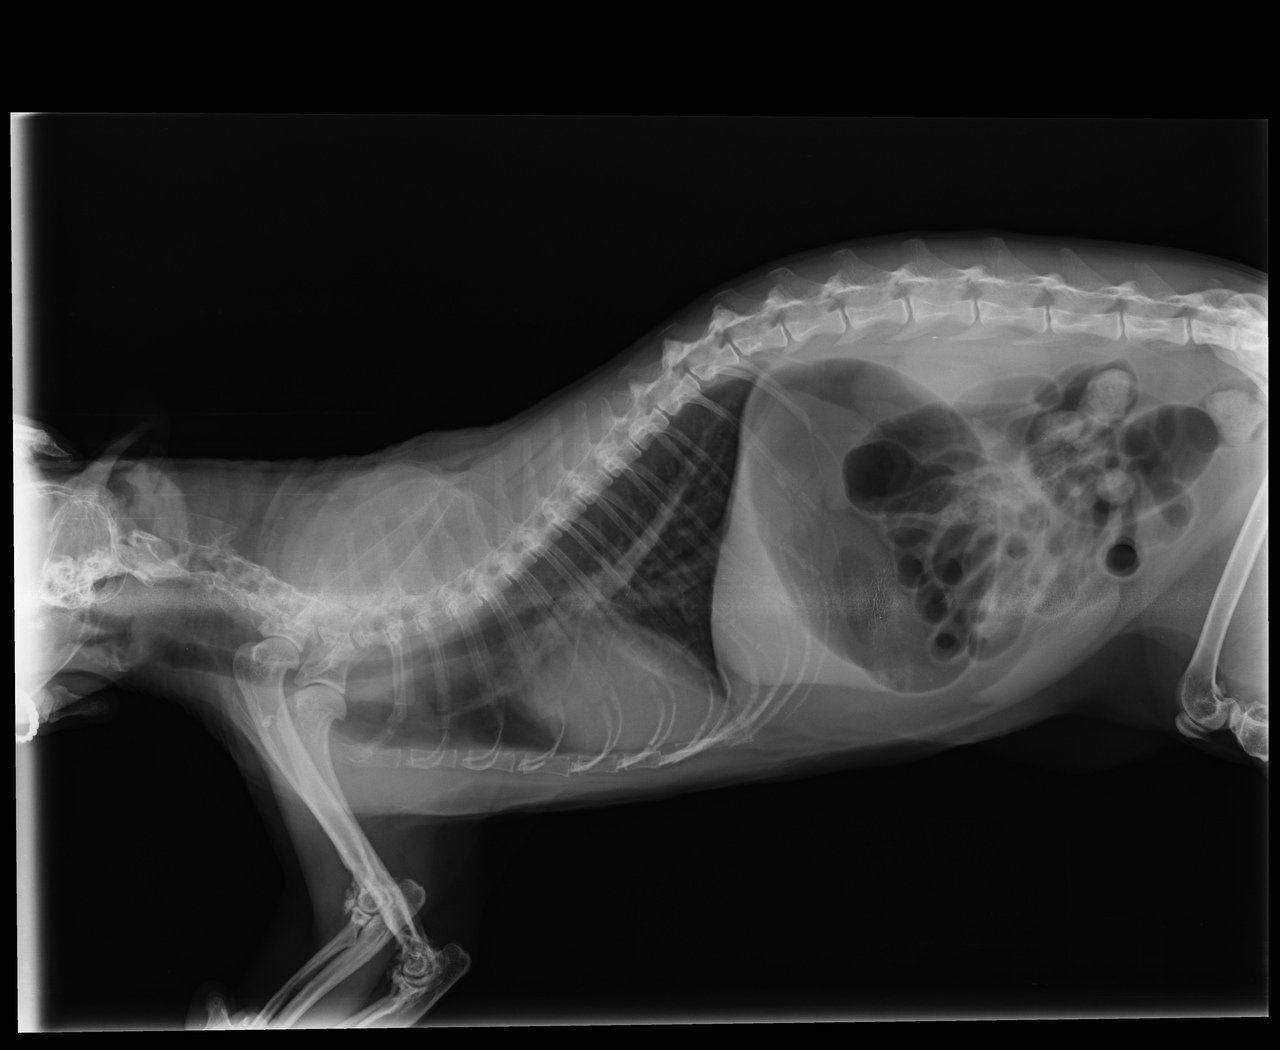

Суставы у шотландских кошек

Суставы у шотландских кошек 106 фото